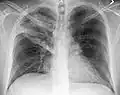

The discovery of x-rays made it possible to determine the anatomic type of pneumonia without direct examination of the lungs at autopsy and led to the development of a radiological classification. Early investigators distinguished between typical lobar pneumonia and atypical (e.g. Chlamydophila) or viral pneumonia using the location, distribution, and appearance of the opacities they saw on chest x-rays. Certain x-ray findings can be used to help predict the course of illness, although it is not possible to clearly determine the microbiologic cause of a pneumonia with x-rays alone.